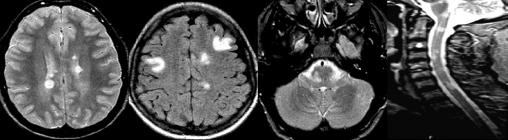

De gauche à droite : périventriculaires, corticales/juxtacorticales, infratentorielles et médullaires. Les lésions périventriculaires doivent être au contact des ventricules et sont ovoïdes et perpendiculaires à l’axe des ventricules. Les lésions juxtacorticales doivent être au contact du cortex.

Avec l’aimable autorisation du Pr. S Vukusic.